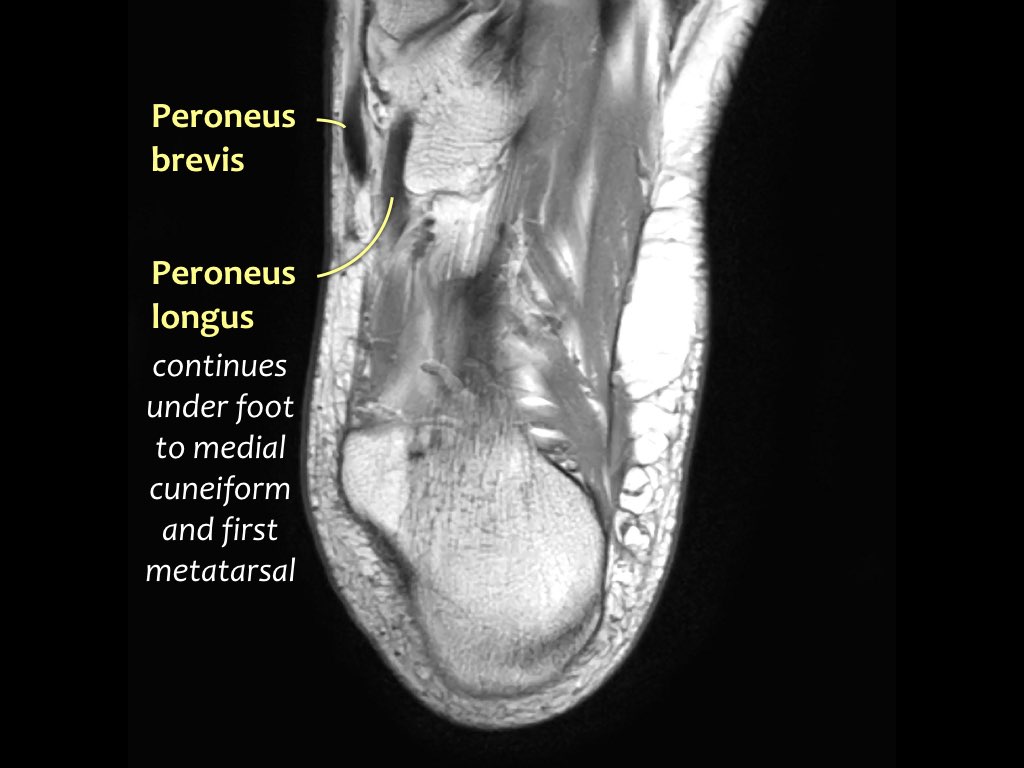

- Khoang ngoài

- Gân cơ mác dài (Peroneus Longus)

- Gân cơ mác ngắn (Peroneus Brevis)